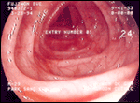

2) ÃâÇ÷ - ÀáÇ÷¼º(º¯¿¡ ¼¯¿© º¸ÀÌÁö ¾Ê´Â °æ¿ì) Àϼöµµ ÀÖÀ¸³ª, ¼±È«»ö ÇüÅ·Π³ªÅ¸³ª´Â ¼ö°¡ ¸¹´Ù. ƯÈ÷ Á÷Àå¾ÏÀÌ °æ¿ì´Â ¼±È«»öÀ¸·Î ³ª¿À±â ¶§¹®¿¡ Ä¡ÇÙÀ¸·Î ¿ÀÀÎÇÏ´Â °æ¿ì°¡ ¸¹´Ù. ÀáÇ÷¼º ÃâÇ÷ÀÌ Áö¼ÓµÇ´Â °æ¿ì ¸¸¼ººóÇ÷ÀÌ ¿À¸ç, Çǰï, Àü½Å¼è¾à Áõ»óÀÌ ¿Ã ¼ö ÀÖ´Ù. 3) º¹Åë - ÈçÇÏÁö ¾Ê´Â Áõ»óÀ̸ç, ÁÖ·Î º¹ºÎÁß¾ÓÀ̳ª ¾Æ·§¹è Á¿ìÃøÀÇ ±íÀº °÷¿¡¼ º¹ÅëÀÌ ´À²¸Áø´Ù. ¿À½É, ¼ÒȺҷ®Áõ¼¼, º¹ºÎÆØ¸¸°¨ µîÀÌ µ¿¹ÝµÉ ¼ö ÀÖ´Ù. 4) ºÏºÎ¸Û¿ì¸® - ȯÀÚÀÚ½ÅÀÌ º¹ºÎ¿¡¼ ¸Û¿ì¸®¸¦ ¸¸Áö°í ¿À´Â °æ¿ìµµ ÀÖ´Ù. 5) üÁß°¨¼Ò 6) Á¡¾×¹èÃâ 1. Àü½Å ¹× º¹ºÎÁøÂû 2. Ç×¹®¼öÁö°Ë»ç - Ç×¹®¿¡ ¼Õ°¡¶ôÀ» ³Ö¾î º¼ °æ¿ì ÇϺÎÁ÷Àå¾ÏÀ» ¸¸Áú ¼ö°¡ Àֱ⠶§¹®¿¡ ÇϺÎÁ÷Àå¾Ï Áø´Ü¿¡ ´ë´ÜÈ÷ Áß¿äÇÏ´Ù. 3. ³»½Ã°æ - Á÷Àå´ëÀå³»½Ã°æ °Ë»ç´Â °¡Àå ½±°í , °¡Àå Á¤È®ÇÏ°Ô Áø´Ü ÇÒ ¼ö ÀÖ´Â ¹æ¹ýÀÌ´Ù. 4. ´ëÀåÁ¶¿°¼ú- ´ëÀå¾È¿¡ ¹Ù¸®¿òÀ̶ó´Â ¾×À» ³Ö¾î¼ x-rayÃÔ¿µÀ» ÇÏ´Â ¹æ¹ý 5. CT ¶Ç´Â MRI 6. °æÁ÷Àå Ç×¹® ÃÊÀ½ÆÄ - ´ëÀå¾ÏÀÌ Áø´Ü µÇ¾úÀ» °æ¿ì ¾ÏÀÌ À庮À» ¾ó¸¶³ª ħ¹üÇÏ¿´´ÂÁö Áø´ÜÇϴµ¥ ÁÁÀº ¹æ¹ýÀÌ´Ù. 7. º¹ºÎ µ¿À§¿ø¼Ò ½ºÄµ 1. ¼ö¼ú - ¾ÏÄ¡·á¿¡ ÀÖ¾î¼ °¡Àå ±Ùº»ÀÌ µÇ´Â Ä¡·á¹æ¹ýÀ¸·Î ¾Ï¸Û¿ì¸®¸¦ Æ÷ÇÔÇÑ ÁÖÀ§Á¶Á÷À» ±¤¹üÀ§ ÀýÁ¦ ÇÏ´Â °ÍÀÌ´Ù. 2. ÈÇпä¹ý ¹× ¹æ»ç¼±¿ä¹ý - ¼ö¼ú¿¡ ´ëÇÑ º¸Á¶¿ä¹ýÀ¸·Î ±ÙÄ¡Àû ¼ö¼ú ÈÄ¿¡µµ ±¹¼Ò ¶Ç´Â ¿ø°ÝÀå±â¿¡ ¹Ì¼¼ ¾Ï¼¼Æ÷°¡ Á¸ÀçÇÒ ¼ö ÀÖÀ¸¹Ç·Î ÀÌ·¯ÇÑ ÀÜÁ¸ ¾Ï¼¼Æ÷¸¦ ¾ø¾Ö¼ Ä¡À¯À²À» ³ôÀ̱â À§ÇÑ °ÍÀÌ´Ù. °áÀå¾ÏÀÎ °æ¿ì Ç×¾Ï ÈÈ®¿ä¹ýÀ¸·Î, Á÷Àå¾ÏÀÎ °æ¿ì¿¡´Â ÈÇпä¹ý°ú ¹æ»ç¼±¿ä¹ýÀ» º´ÇàÇØ¼ »ç¿ëÇϰí ÀÖ´Ù. |